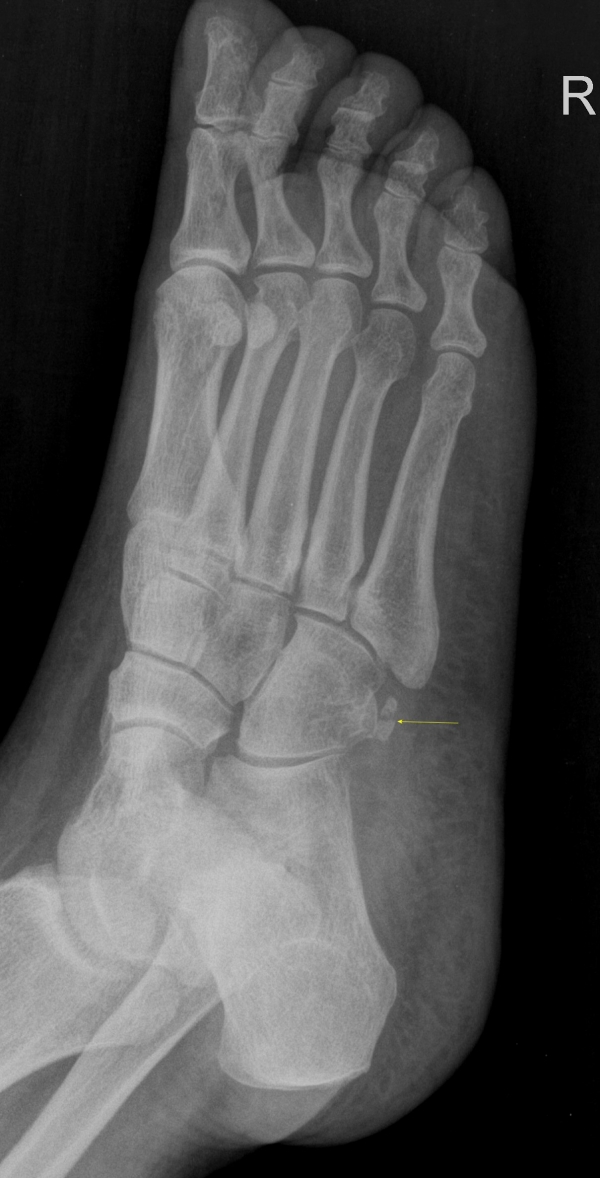

´Ü¼ø¹æ»ç¼±°Ë»ç

ºñ°ñ°ÇÀÇ °ñÀýÀÌ ÃßÁ¤µÇ´Â ¾ç»ó

os peroneum Àº ¾à 30%¿¡¼­ À̺ÐÈ­(bipartiate)¸¦ ´Ü¼ö³¶»ç¼± ÃÔ¿µ¿¡¼­ µÎ Á¶°¢À¸·Î

º¸ÀÌ´Â °æ¿ì °ñÀýÀÎÁö ¾Æ´Ï¸é Á¤»óÀûÀÎ À̺ÐÈ­ÀÎÁö¸¦ °¨º°ÇØ¾ß ÇÑ´Ù.

ÀÌÇÐÀû °Ë»ç»ó ±¹¼ÒÀûÀÎ ¾ÐÅë, ¹æ»ç¼± ÃÔ¿µ¿¡¼­ Á¾ÀÚ»ÀÀÇ Çü»óÀ¸·Î ¾î´À Á¤µµ °¨º°Àº °¡´ÉÇÏÁö¸¸

ÃÊÀ½ÆÄ°Ë»ç¸¦ ½ÃÇàÇÏ¸é º¸´Ù È®½ÇÇÏ°Ô °¨º°Áø´ÜÀÌ °¡´ÉÇÏ´Ù.

ÃÊÀ½ÆÄ°Ë»ç»ó Á¾ÀÚ»À³ª ºñ°ñ°Ç ÁÖÀ§ÀÇ ºÎÁ¾, Á¾ÀÚ»ÀÀÇ Ç¥¸éÀÇ °ÅÄ£Çü»ó, ºñ°ñ°ÇÀÇ ºÎÁ¾À̳ª ÆÄ¿­ÀÌ °üÂûµÉ ¼ö ÀÖ´Ù.